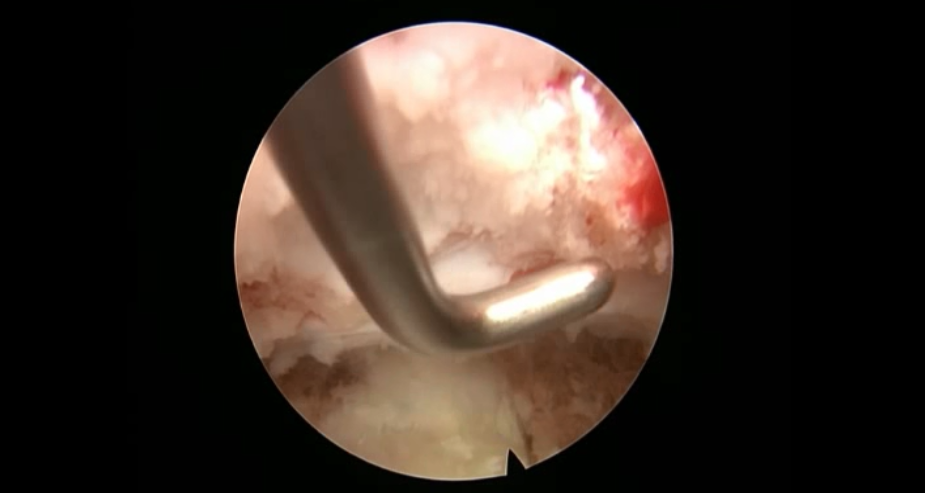

术中资料

点击以上图片,查看术中视频(超链接:http://res.orthonline.com.cn/video/case5---20.mp4)